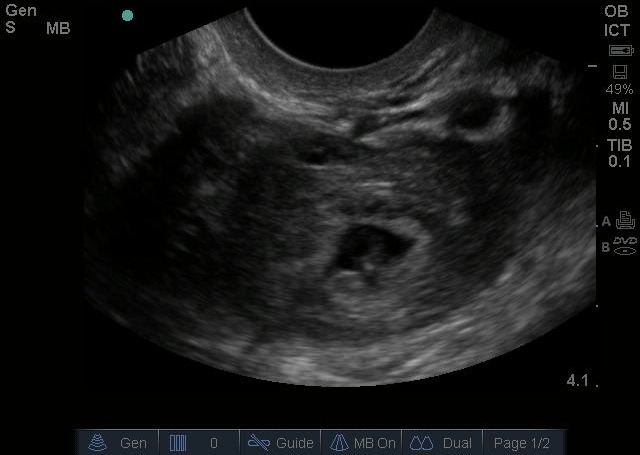

Bild 2: Transvaginaler (TV) Ultraschall des Beckens, ektopische Schwangerschaft, Adnexe